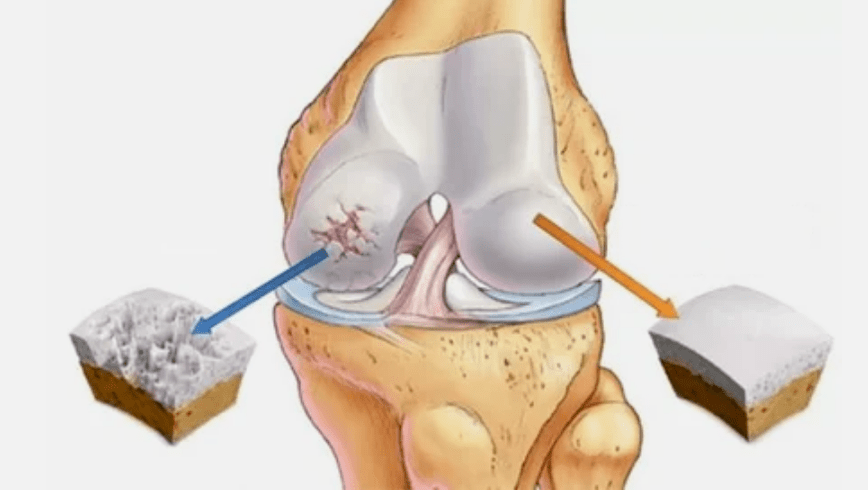

L'arthrose de l'articulation se développe longtemps, n'affecte initialement que le Hyalink NORP puis se propage aux os, le bol synovial, les muscles et la capsule articulaire entière, contient. Au premier ou au début de l'arthrose, la lésion se manifeste facilement: petite douleur après travail acharné, gonflement, rougeur de la peau. En raison de l'ignorance, les sensations désagréables sont déformées, enflammées et apporte une douleur intense, son point culminant tombe le matin. La maladie se caractérise par la disparition de la douleur après le développement de l'articulation. S'il n'est pas traité, une personne perd complètement la mobilité de l'articulation.

- Pathologies de revêtement Hyalin. L'amincissement du cartilage conduit au remplacement de ses tissus pathologiques - structures osseuses.

- La croissance anormale apparaît sur le cartilage - ostéophytes.

- La violation de l'anatomie naturelle du cartilage et des os conduit à la surcharge de zones de cartilage saines. La destruction des tissus articulaires sans traitement continue de conduire et entraîne des handicaps.

Si le degré de maladie augmente, les processus pathologiques sont encore pires. En fin de compte, l'ensemble du Hyalink Norp est détruit.